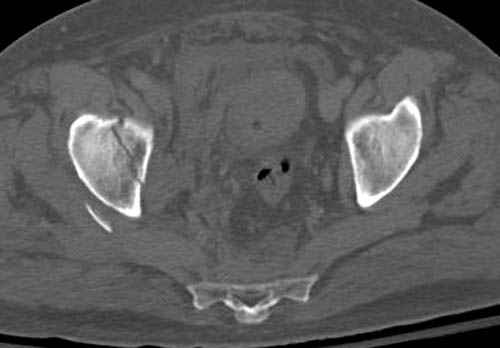

По возможности вышлите снимки, сканы таза до

реконструкции, интраоперационные.

По снимку создается впечатление о высоком поперечном переломе, задней колонны, стенки; почему не пользовались *magic screw*?

Снимки здесь....